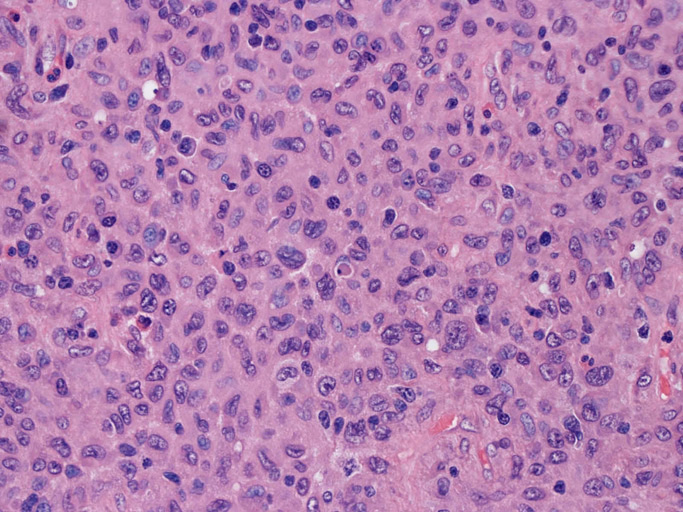

LCSの病理組織所見

Langerhans cell histiocytosisの高悪性度 variantで明らかな悪性像を示すLangerhans cellの腫瘍性増殖と定義される(WHO, 2008)

大型細胞の増殖よりなる腫瘍。縦溝,しわ,切れ込みのある核をもった大型細胞も出現する。クロマチンは顆粒状で核小体も明瞭である。核分裂は >50/10hpfと多い。eosinophilsは少ない。壊死が多発することがある。未分化ないし低分化な細胞像, 組織所見のため鑑別診断は多岐にわたり、的確な免疫染色を行う必要がある。